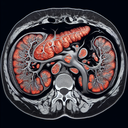

МРТ органів черевної порожнини

Магнітно-резонансна томографія (МРТ) органів черевної порожнини – це неінвазивний метод діагностики, який використовує магнітне поле та радіохвилі для створення детальних зображень внутрішніх структур черевної порожнини. Цей метод допомагає лікарям оцінити органи, такі як печінка, підшлункова залоза, нирки, селезінка і жовчні шляхи. ### Підготовка до МРТ черевної порожнини: 1...